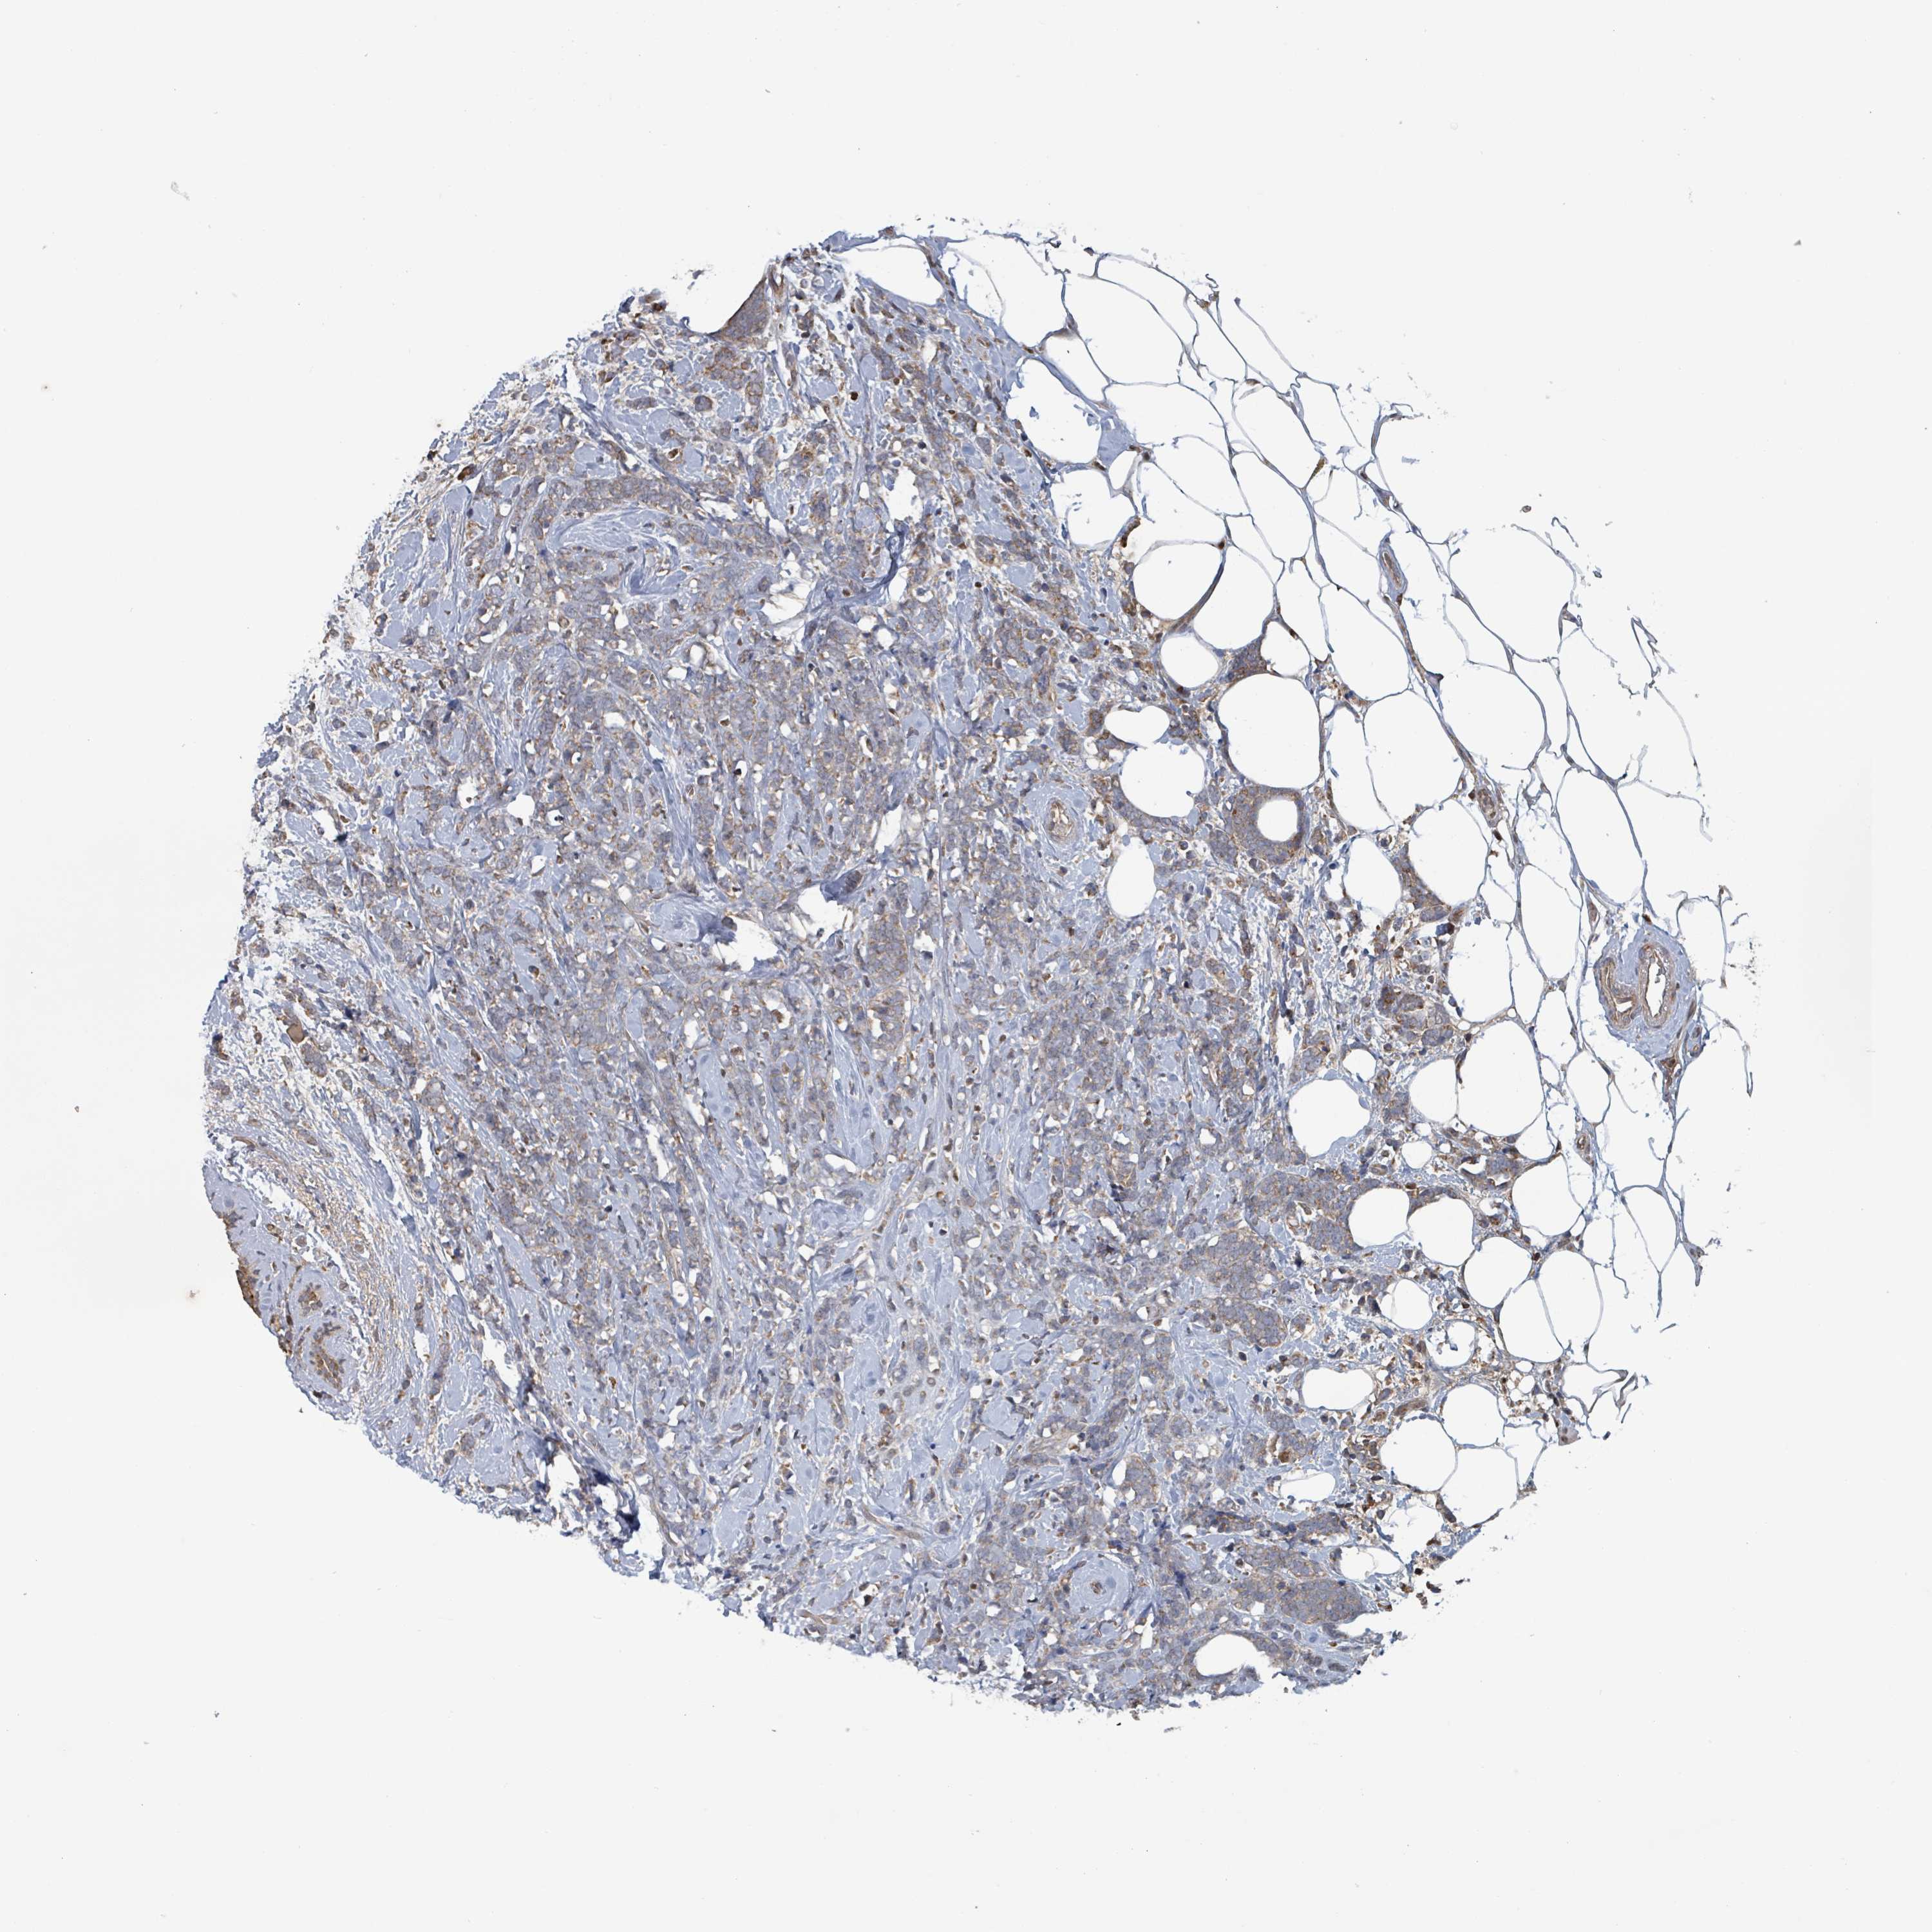

CANCER BREAST CANCER Show tissue menu

BRCA TCGA BRCA VALIDATION PROTEIN EXPRESSION

ANTIBODIES

AND

VALIDATION